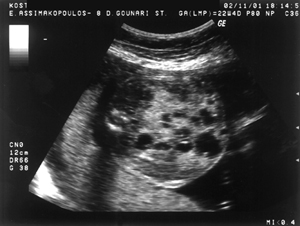

Εικόνα 1. Εκτεταμένη διάταση

του εντέρου του εμβρύου, με πολλαπλές εντερικές έλικες γεμάτες με υγρό στο υπερηχογράφημα

στις 22 εβδομάδες της κύησης.

Εικόνα 2. Παρόμοια εικόνα

διάτασης του εντέρου του εμβρύου, από άλλη τομή, στις 22 εβδομάδες της κύησης

(εικόνα 1).

και βρέθηκε φυσιολογικός καρυότυπος θήλεος εμβρύου (46ΧΧ). Στις 22 εβδομάδες

στην εξέταση ρουτίνας του δευτέρου τριμήνου για εμβρυϊκές ανωμαλίες (υπερηχογράφημα

18-23 εβδομάδων) διαπιστώθηκε εκτεταμένη διάταση του εντέρου, με πολλαπλές εντερικές

έλικες γεμάτες υγρό στην κοιλιακή χώρα (εικόνες 1,2). Δεν σημειώθηκαν παθολογικά

ειλεού διακρίνονται ως πολλαπλές, διατεταμένες έλικες εντέρου γεμάτες υγρό εντός

της κοιλίας.(32) Αυτήν ακριβώς την εμφάνιση είχε και το αιμαγγείωμα στην παρούσα

περίπτωση (εικόνα 1).